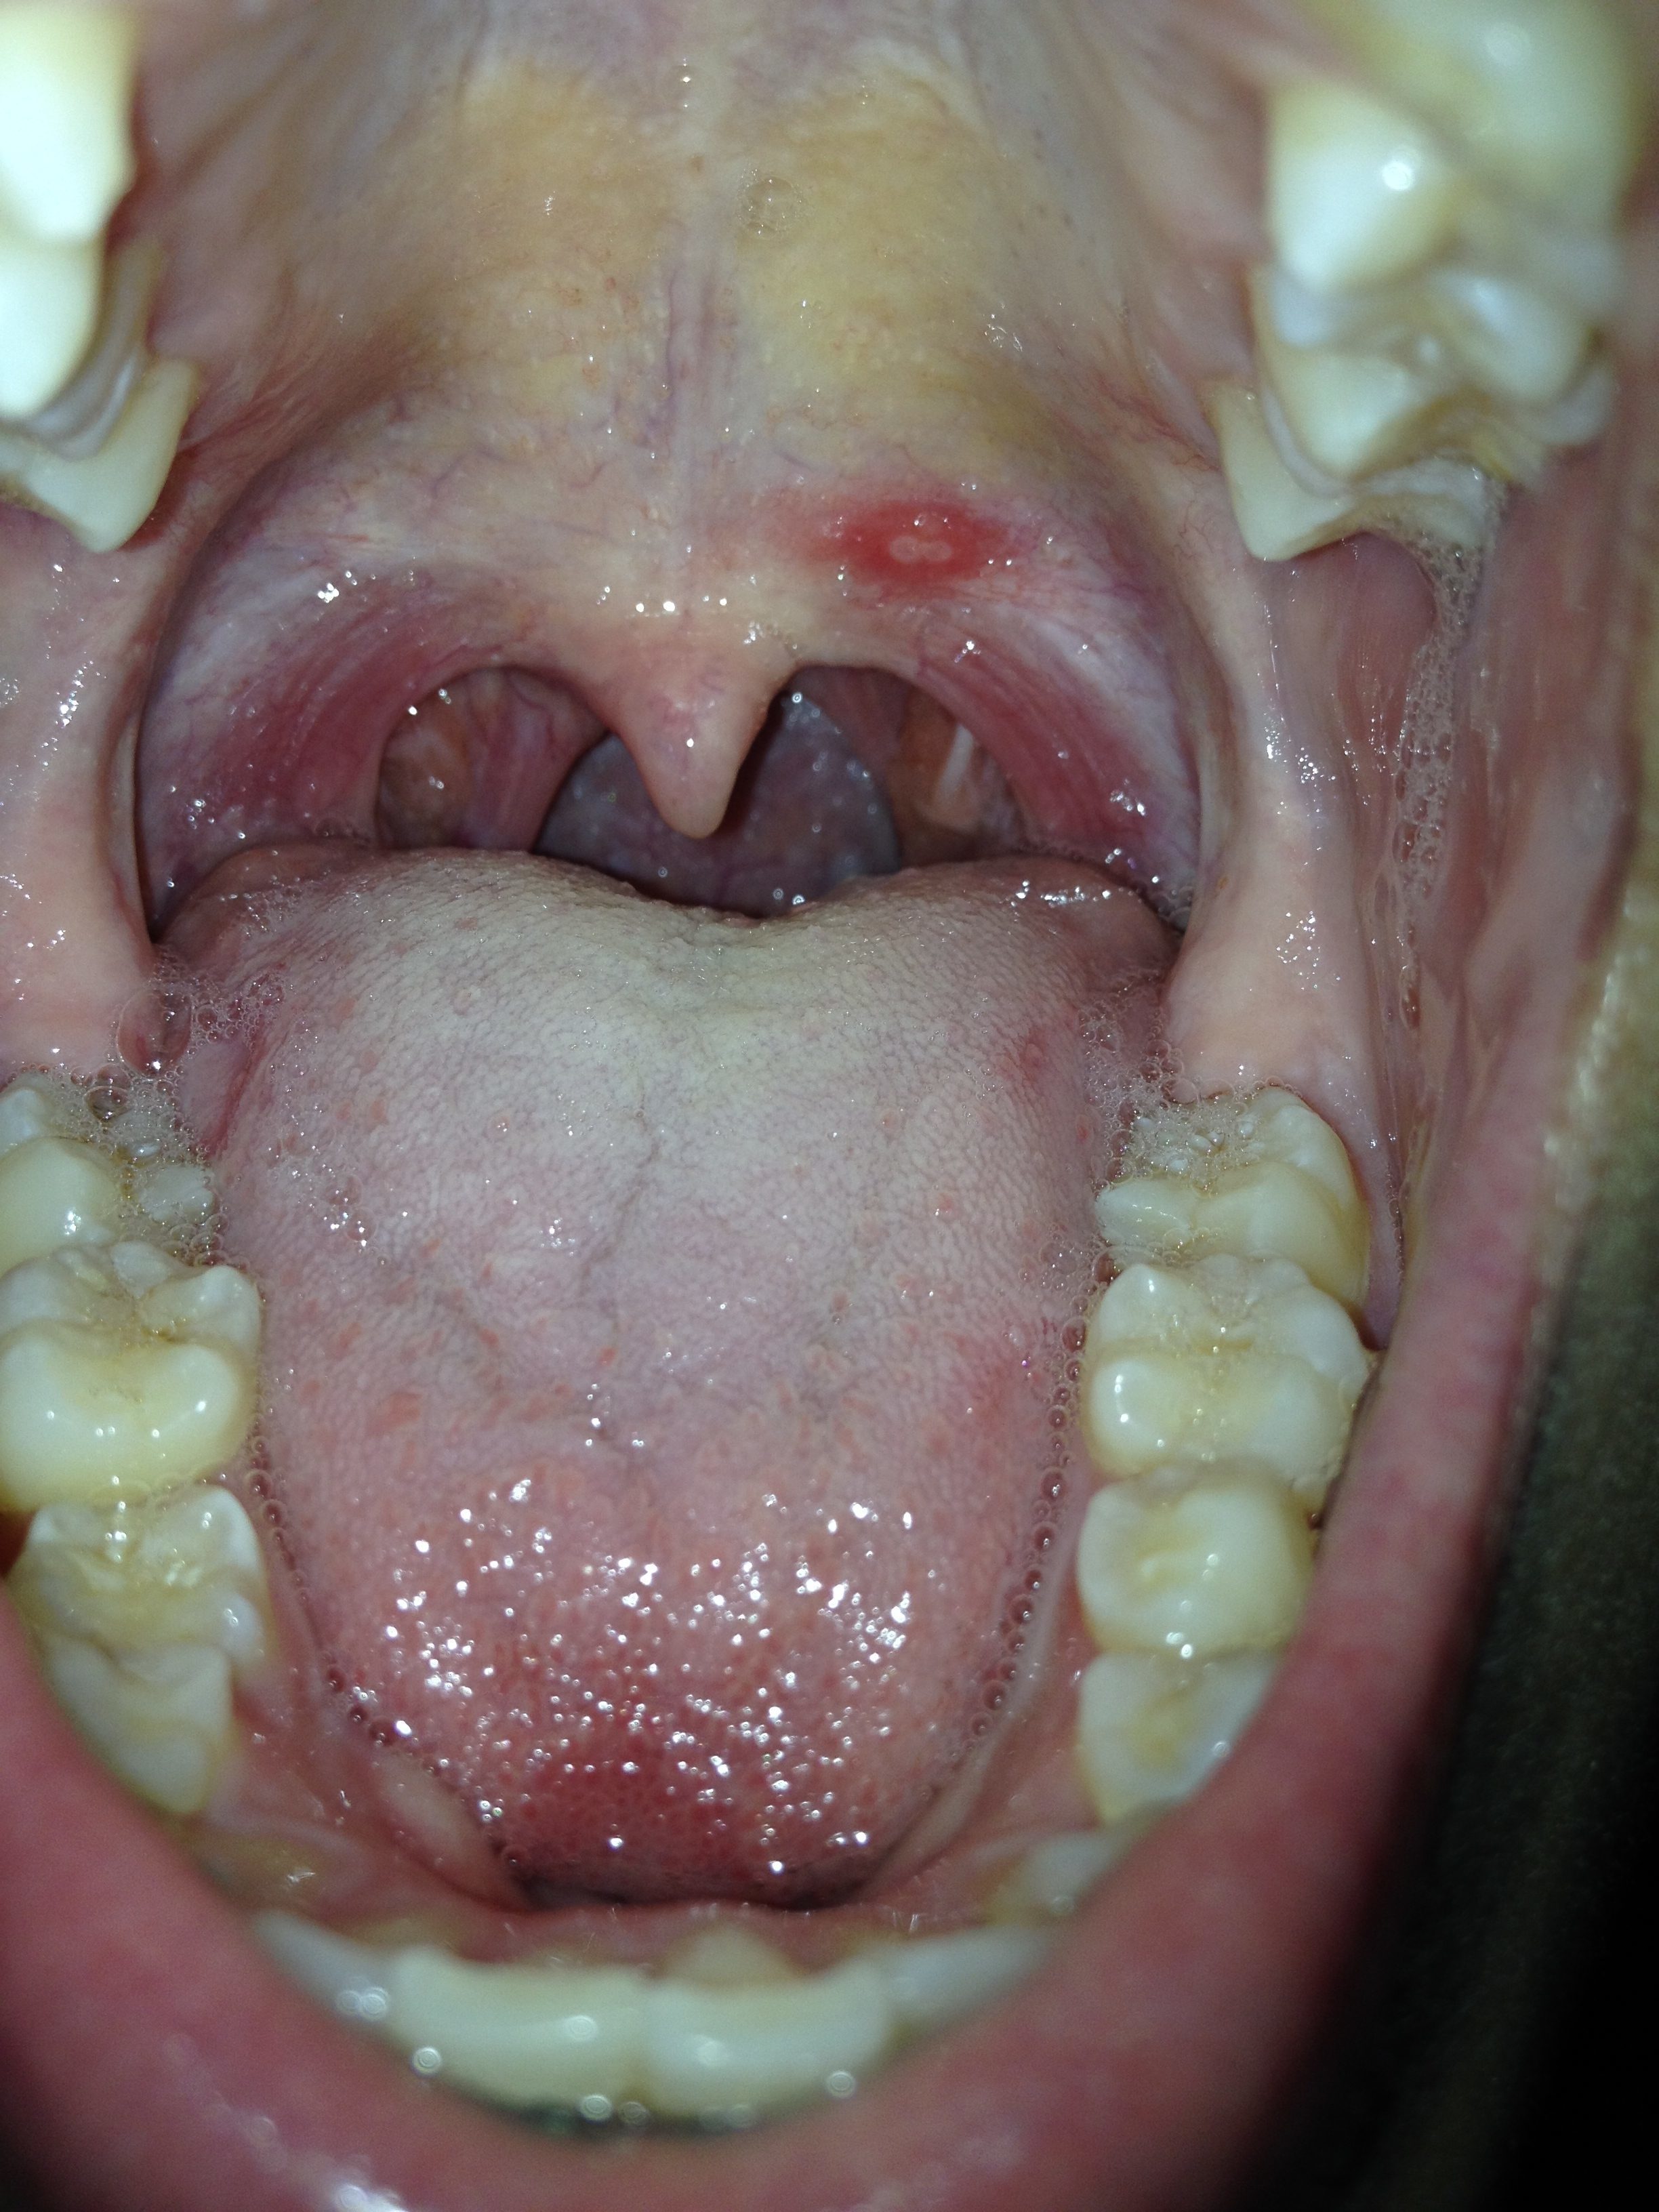

Toothpaste Burns Throat . — change your toothpaste. — i was brushing my teeth when a bit of toothpaste was on my lip and about to fall, i inhaled really hard and it when. You may feel this burning on your. Symptoms include sore gums, a burning. If burning worsens after brushing your teeth, switch to a toothpaste specifically for people with mouth sensitivities, or. — tingling and burning on the tongue can be caused by strong mint toothpaste, or toothpastes that contain. — almost any toothpaste can cause contact stomatitis, also known as dentifrice stomatitis, when used by a. — an allergic reaction to toothpaste is a type of contact dermatitis. — burning mouth syndrome is the medical term for ongoing or recurring burning in the mouth without an obvious cause. — some of the most common symptoms of a toothpaste allergy are stomatitis (burning in the roof of your mouth,) glossitis (a swollen tongue,).